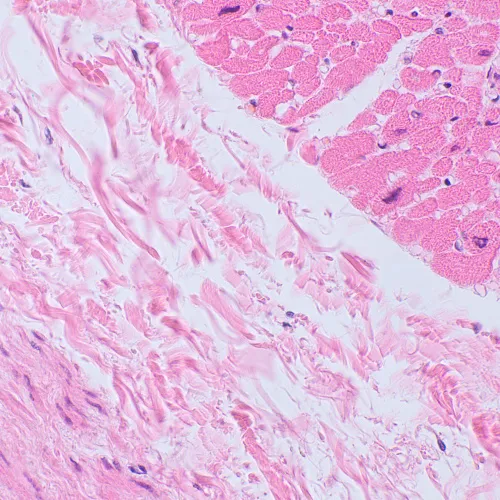

Микроскопът MAGUS Bio 250BL може да се използва за лабораторна работа, научни изследвания и обучение на студенти. Той е предназначен за наблюдение на тънки разрези и натривки на биологични образци с преминаваща светлина. Основният метод за наблюдение е този на светлото поле, но също така могат да се използват методите на тъмно поле, поляризация и фазов контраст (с допълнителни принадлежности).

Диапазонът на увеличение на микроскопа е от 40x до 1000x. Горната граница на увеличението може да се увеличи чрез добавяне на допълнителни окуляри.